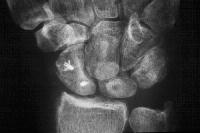

Preop

Click for larger image

Postop.

Case 4. Preop dynamic instability

Lucency where a screw lies.